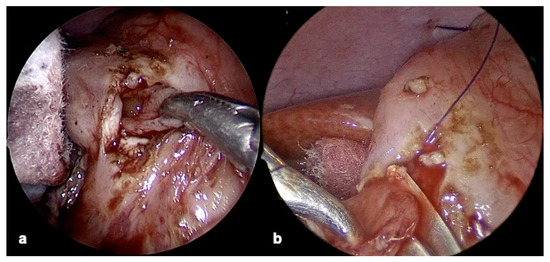

2.4.2. Laparoscopic Resection

2.4.3. Duodenal Web Localization